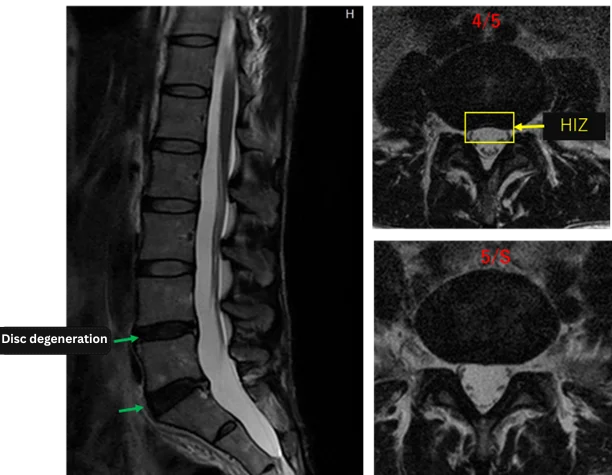

Imaging and findings

L1/2: Normal

L2/3: Normal

L3/4: Normal

L4/5: Disc degeneration, bulging, annular tear

L5/S: Disc degeneration, bulging, annular tear

The above findings were also observed on the imaging.

Disc degeneration and annulus fibrosus tears found at L4/5 and L5/S are highly likely the cause of the primary symptoms.

The image above shows the discs after the Discogel injection.